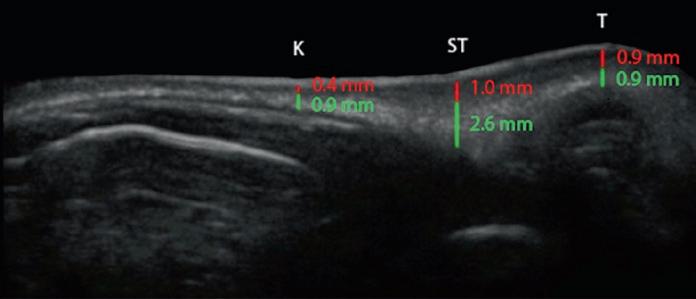

Sonogram analysis of the nasal skin is an extremely valuable tool, both for preop and postop analysis in rhinoplasty surgery. Patients found to have thin skin had a dermal thickness at the keystone junction (K) of 0.2 mm (0.1–0.4 mm), compared with 0.36 mm (0.28–0.40 mm) for normal skin and 0.48 mm (0.42–0.63 mm) for thick skin (Fig. 1.20) (Kosins and Obaghi 2017). This difference in thickness also existed in the supratip and tip areas, but these areas were also affected by the oiliness of the skin. Overall, patients with skin that was determined to be oily had a dermal thickness that was 25% thicker at the supratip and 34% thicker at the tip area. Soft tissue thickness underlying the dermis was variable. Patients of non-Caucasian background were more likely to have a thicker soft tissue layer. Patients with thick skin can be divided into those with thick dermis, thick underlying soft tissue, or both.

Fig. 1.20 Sonograms of nasal skin, showing the thickness of the dermis (red ) and SMAS ( green). (a, b) Thin skin. (c , d) Medium skin. (e, f ) Thick skin. K keystone junction; ST supratip; T tip (Sonograms courtesy of Aaron Kosins, MD.)